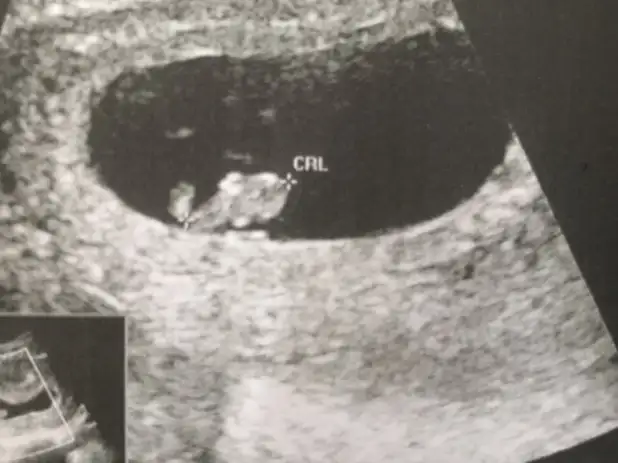

Canım bir de bu varmış 8 haftalık bunu yorumlayabilir misinÖgrendinizmi

Ayy canım kusura bakma unutmuşum eklemeyi8 haftalık varmış dediniz bende usg göremedim dedim

Buna göre kızAyy canım kusura bakma unutmuşum eklemeyi